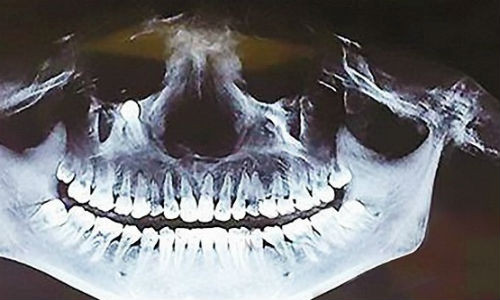

Các bác sĩ đã chụp X-quang, chẩn đoán chính xác. Sau đó, bác sĩ nhổ được một chiếc răng trong mũi của trẻ trước sự ngạc nhiên của bố mẹ.